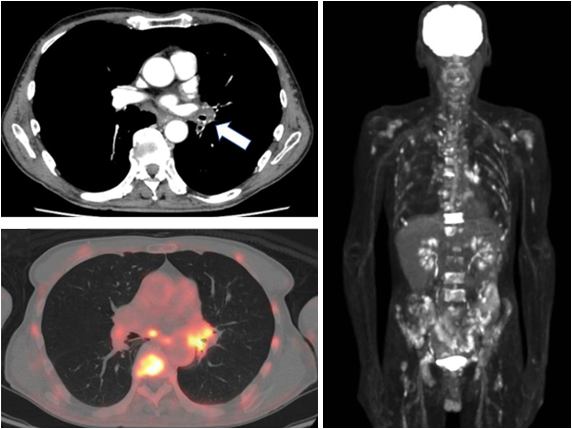

治疗前PET-CT影像

在启动治疗后的24周,患者完成整个治疗疗程,研究组通过影像评估了患者治疗前后骨转移灶的变化。

通过PET-CT检测,我们发现患者的脊柱、双侧股骨及肱骨的转移灶均得到有效控制,患者实现了完全缓解。